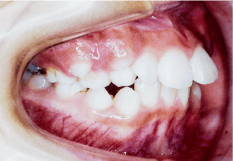

この状態だと前歯でくちびるを切ってしまったり、顔を強打したときに歯が折れやすくなります。 - 下顎前突(がかくぜんとつ)

- 出っ歯とは逆に、上の歯より下の歯が前面に出ている状態で、上の顎が小さい、もしくは下の顎が大きいことで起こります。うまく食べ物が噛めなかったり、滑舌が悪くなる歯並びです。